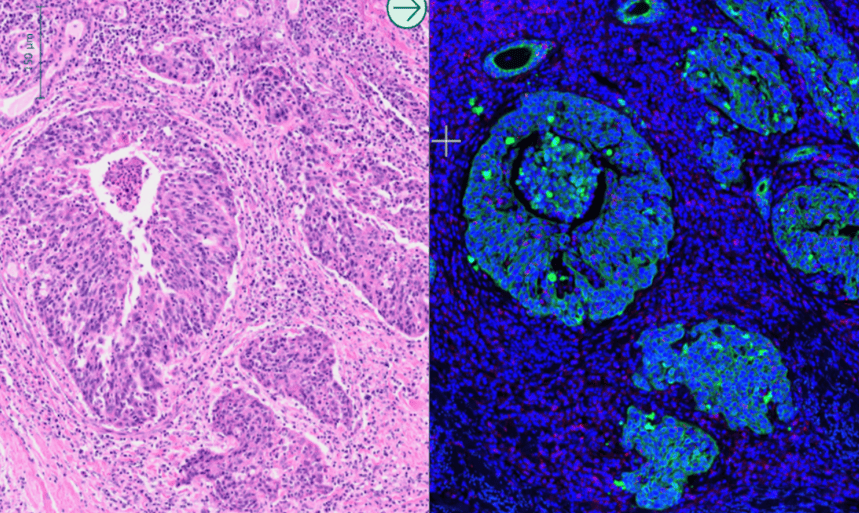

- Use an H&E and/or immunofluorescence (IF) stained image to mark up the tissue and identify functional structures and cell types, making ROI selection simpler and faster.

- Overlay the marked-up image with the GeoMx image for rapid ROI transfer using the Tissuealign module.

Oncotopix Discovery can enhance enrichment for GeoMx profiling to get a cleaner profiling signature from selected tissue compartments.